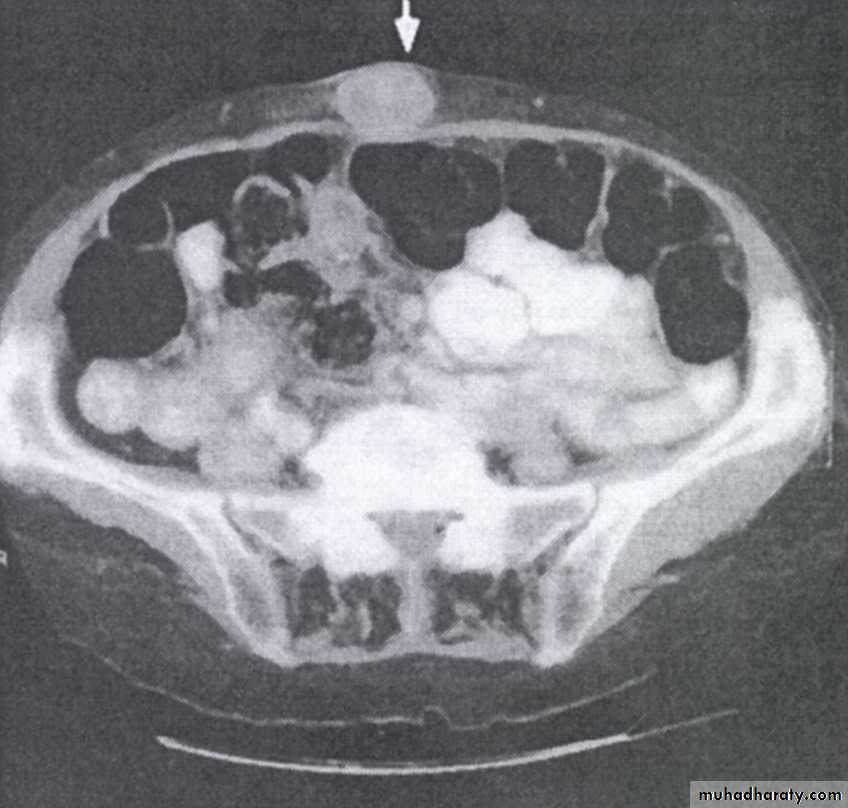

CT abdomen: show evidence of intra-abdominal spread or liver metastases.

Krukenberg tumors: Bilateral ovarian tumors (arrows). These represent ovarian metastases from a gastric adenocarcinoma.